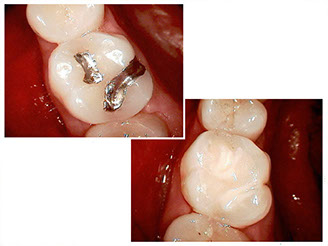

Composite fillings

Composite, or white fillings, have been used in dentistry for several decades. This material involves an organic resin mixed with an inorganic filler to give it strength.